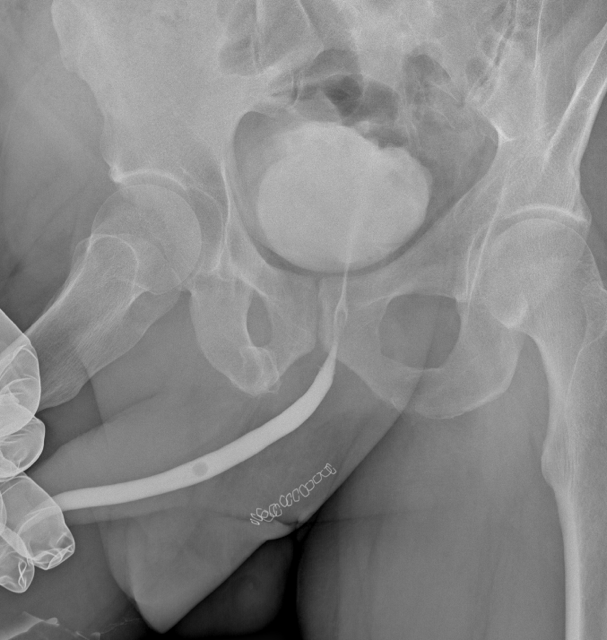

Суть предложенной операции состоит в удалении пораженного сегмента или рубцовых тканей мочеиспускательного канала и соединении между собой здоровых концов уретры. Такая операция в наших руках занимает не более 2 часов. При благоприятном течении ближайшего послеоперационного периода пациент на следующие сутки после операции выписывается домой с установленным уретральным катетером. Находясь дома, пациент принимает антибиотик и периодически посещает врача (не более 1  –  2 раз за 10 – 14 дней после операции), что необходимо для полного заживления зоны операции, или уретрального анастомоза. В нашем случае на 12 сутки после операции пациенту была выполнена контрольная уретрография.

Рис. 3. Уретрография пациента на 12 сутки после операции.

Исследование показало отсутствие подтекания контраста и какой-либо деформации мочеиспускательного канала в зоне бывшей стриктуры. На снимке даже не видно следов большой реконструктивной операции; единственное, что напоминает о ней, – это металлические скобки, использованные для ушивания кожной раны, которые хорошо видны в проекции промежности. Сразу после удаления уретрального катетера и заполнения мочевого пузыря пациент свободно помочился. Ниже представлен график урофлоуметрии.